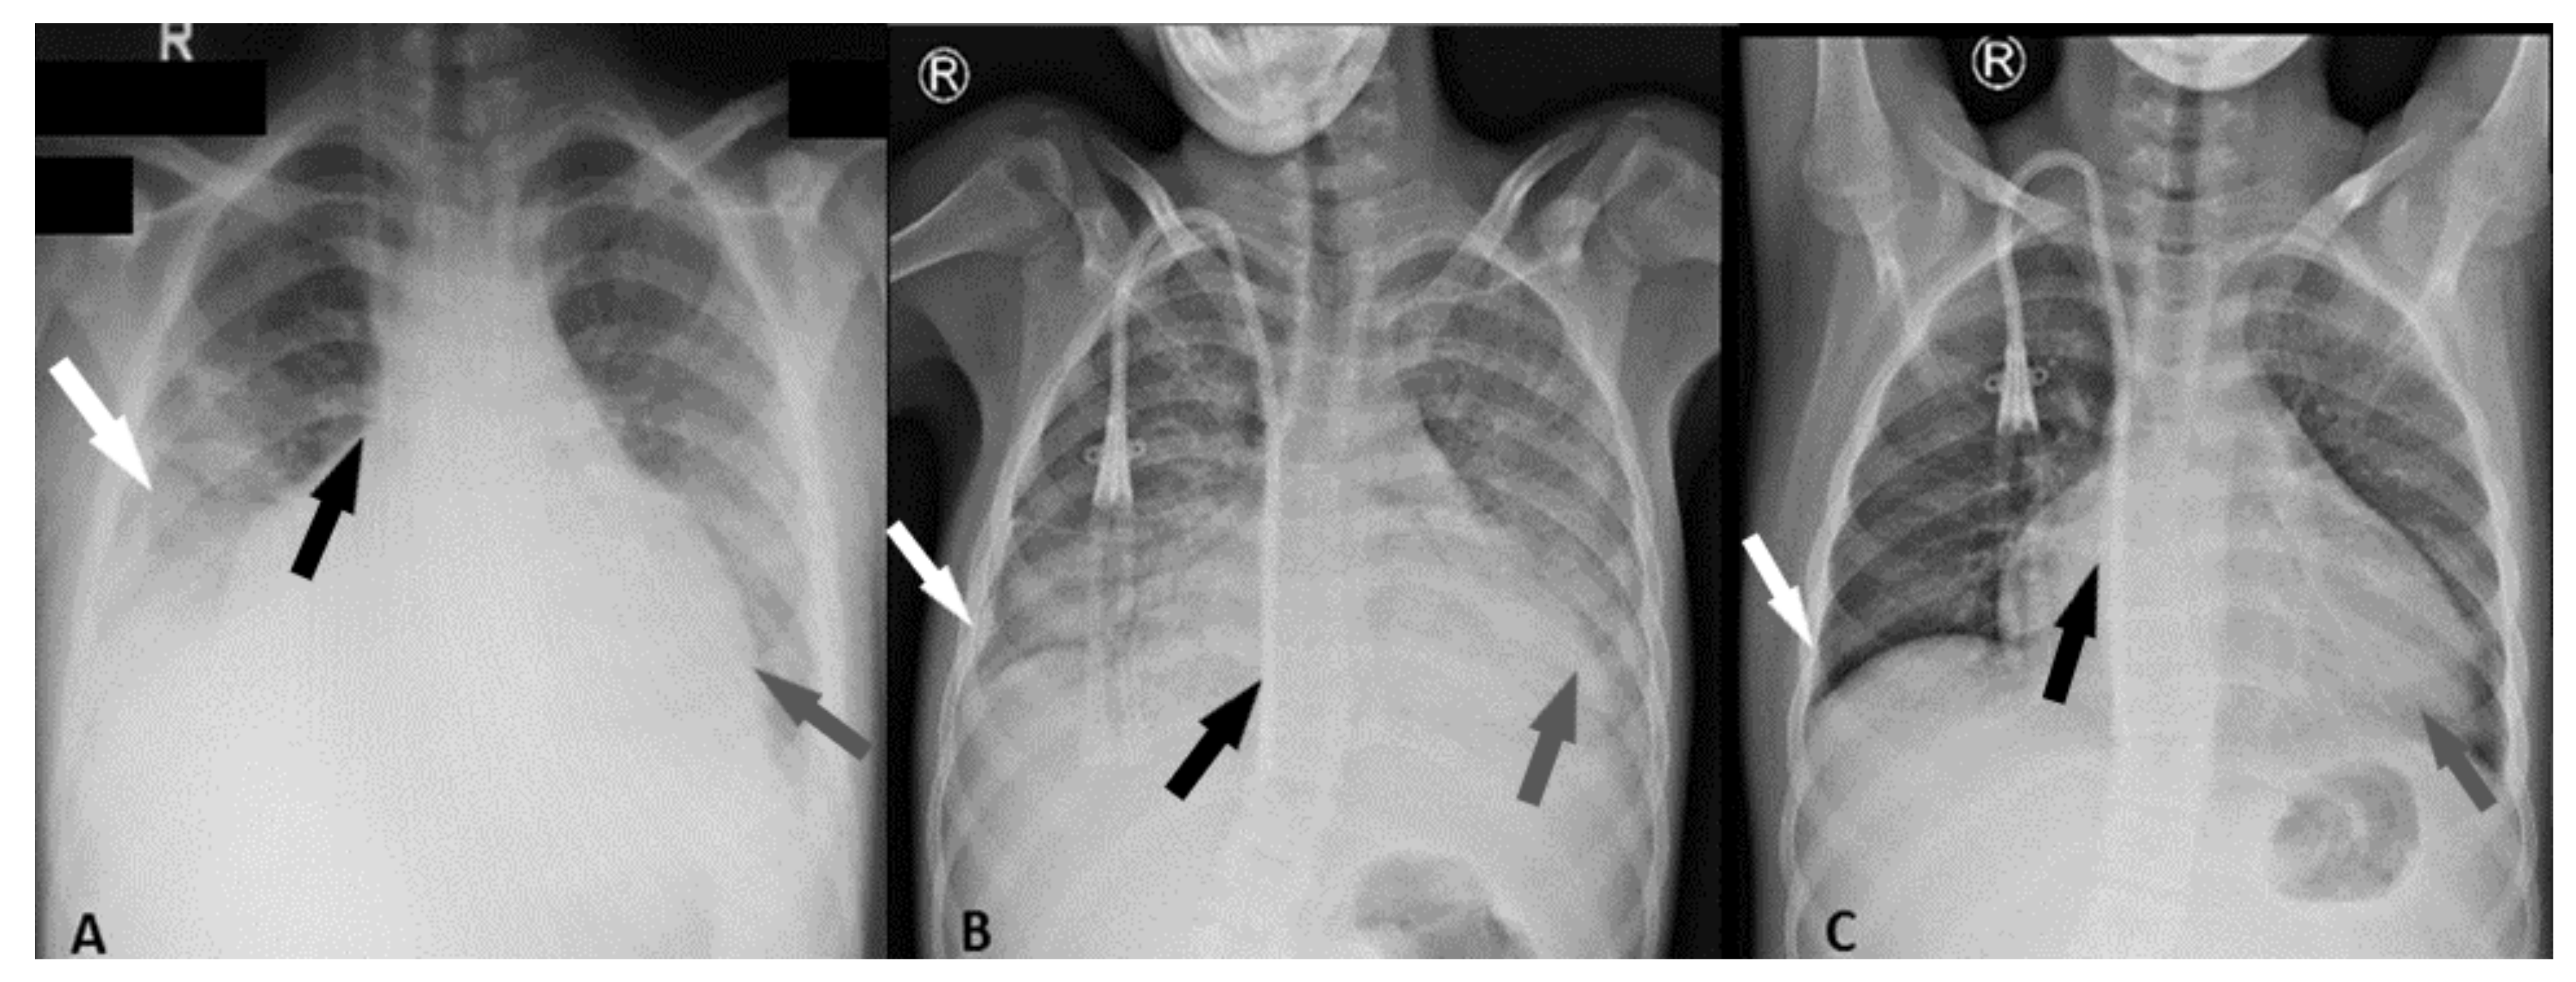

| Pericardial fluid (edge) | <5 mm | Small (6 mm) | Raised (20 mm) | Moderate (14 mm) | Large (22 mm) |